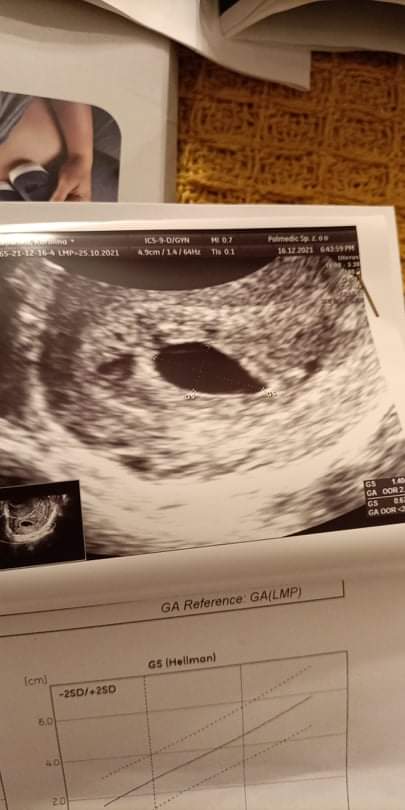

Witam , wczoraj miałam robione USG według OM jestem w 7 tygodniu i 3 dniu ciąży a zarodka brak , pęcherzyk ma wielkość 12 mm . Lekarz stwierdził że może okazać się że ciąża jest po prostu wcześniejsza i dlatego nie widać zarodka , licząc po odbytym stosunku wychodzi na to że jest to albo 4 tydzień i parę dni albo 3 tydzień i parę dni , jednak wiadomo do zapłodnienia może dojść nawet po 7 dniach od stosunku więc patrząc tym tokiem moze być jeszcze wcześniejsza ciąża . Jednak nie ukrywam że martwi mnie fakt że zarodka jeszcze nie ma . Czy któraś z Pań była w podobnej sytuacji ? W którym tygodniu ciąży miałyście ta wielkość pęcherzyka ciążowego ?

A masz zdjęcie z USG? Zarodka bark a był pęcherzyk żółtkowy.?

Pęcherzyk żółtkowy pojawia się ok. 5 tyg + 2 dni do 5 tyg + 5 dni. Zazwyczaj gdy pęcherzyk ciążowy(GS) ma średnicę 8-10 mm.. Pęcherzyk żółtkowy odżywia zarodek który pojawia się parę dni po pojawieniu się żółtkowego..